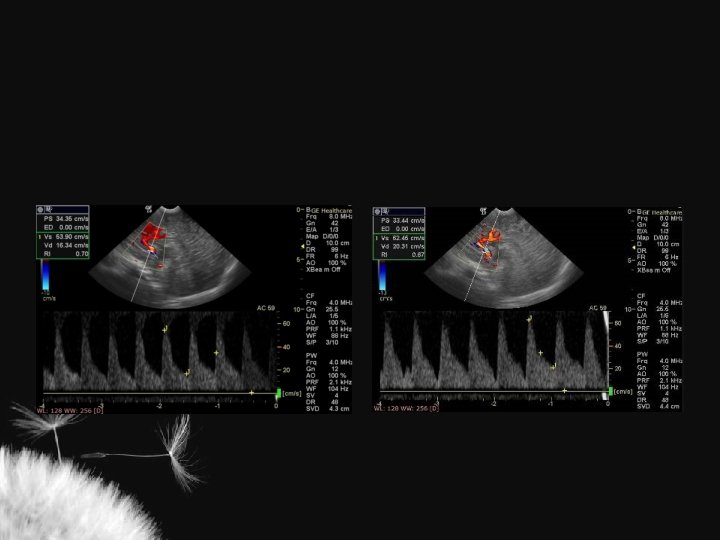

Hidrocefalia benigna da infância – sinal da veia cortical positivo

Coleção subdural – sinal da veia cortical negativo